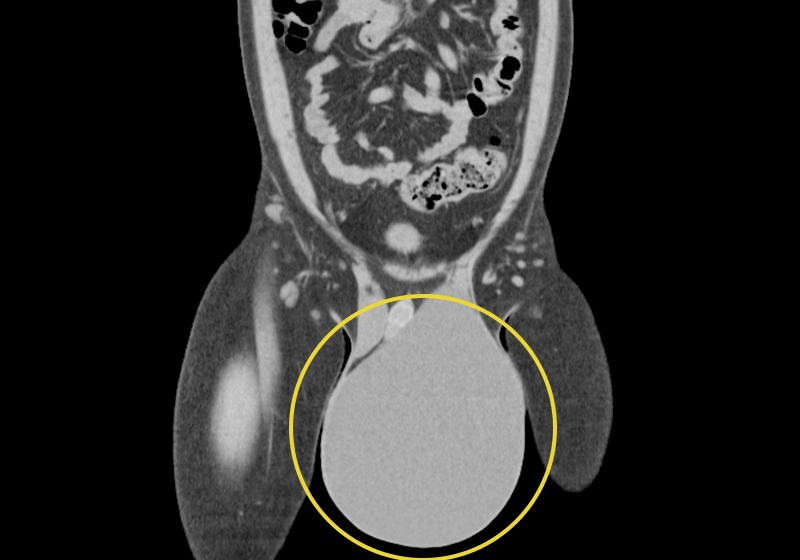

また、精巣腫瘍が原因で陰嚢水腫が生じることがあるため、精巣腫瘍の可能性を否定できない場合には、追加のC T検査やMRI検査等の画像検査と腫瘍マーカーなどの血液検査を行うことがあります。

陰嚢水腫は精巣(睾丸)を包む膜(精巣固有鞘膜といいます)の中に水(リンパ液)が溜まり、陰嚢が膨らんだ状態になる病気です。男性であれば子供から大人まで全ての年齢層で起こる良性の病気で、「鼠径部から陰嚢が膨らむ」という症状が鼠径ヘルニアに類似しているのが特徴です。成人の陰嚢水腫については、原因がはっきり分かっていません。外傷や感染などにより生じた精巣固有膜の病的状態(液体の分泌と吸収のバランスが崩れている状態)等が、要因と考えられています。根治するためには手術が必要となります。

大きさの変化: 腫れの大きさは様々で、鶏卵大から時には新生児の頭ほどにまで大きくなることもあります。交通性の場合、体位(立ったり座ったり)によって大きさが変わることがあります。

超音波(エコー)検査: 最も確実な検査方法です。超音波を使って陰嚢の内部を画像化し、溜まっている液体や精巣の状態を詳しく確認します。精巣腫瘍など他の病気との鑑別も正確に行えます。